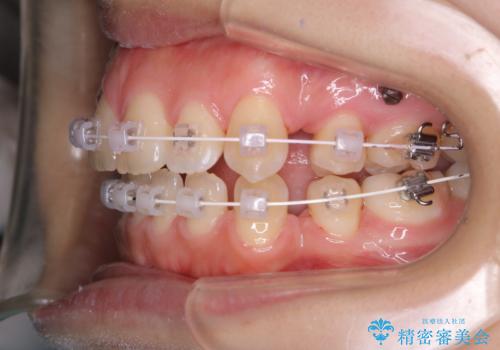

ワイヤー矯正中のクリーニング

- ワイヤー矯正中に、磨ききれないところがあるのと、口臭が気になるとのことでした。

そのためPMTC30分コースを行いました。

ワイヤー矯正中は、装置の周りに汚れが付きやすく虫歯や歯周病のリスクが高まります。そのため、ワイヤー調整の診察の際、一緒にクリーニングを行うことで、虫歯・歯周病・口臭予防になります。歯ブラシだけでは取り除くことが難しい細かい部分などに、専門的な機械や機材を使用して定期的なケアを行うことをおすすめしています。